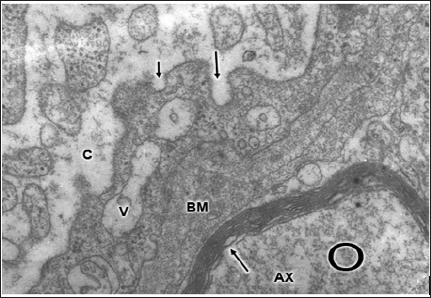

Figure 13: Anomaly of anterior cerebral artery. Left parietal cortex. Astrocytic end-feet (A) showing extensive and undulated interastrocytary gap junction and membrane domains with fusion of both confronted membranes (long arrows). Note the vacuolization (V) and swelling of perivascular astrocytic end feet, and the dense capillary basement membrane (BM). The pericyte cytoplasm (P), the endothelial cell (EC), and the capillary lumen (L) are also distinguished. X 36.000.

Disruption and disassembly of interastrocytary gap junctions have been observed by us in human edematous cerebral cortex of patients with traumatic brain injuries and brain tumors [98] (Figure 13).